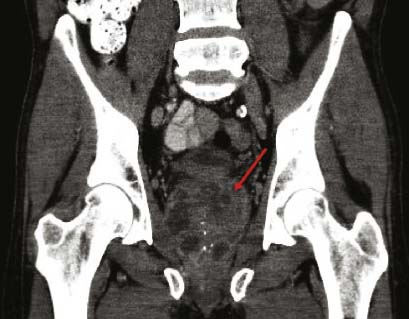

Hình 3.

Hình ảnh chụp cắt lớp đứng ngang (Coronal computed tomography)của một người đàn ông

chủng tộc Caucasian, 62 tuổi, với một áp-xe tuyến tiền liệt lớn (mũi tên), sau chuyến du lịch gần đây tới Thái Lan.

Người này đã mắc melioidosis lan tỏa cấp tính.

Các đặc điểm lâm sàng của melioidosis bắt chước nhiều căn bệnh khác (vd nhiễm trùng máu/sốc nhiễm trùng, viêm phổi mắc từ cộng đồng [CAP] và lao phổi,điều này khiến các bác sĩ thường xuyên chẩn đoán sai căn bệnh này.5  !important;Vì vậy, melioidosis được biết như là ‘kẻ bắt chước vĩ đại’.1 Thời gian ủ bệnh trung bình là chín ngày (1–21 ngày) nhưng các triệu chứng có thể xuất hiện nhanh hơn (<24 giờ) sau khi hít phải và/hoặc sặc nước nhiễm bệnh.1,9 Trong các ca bệnh cấp tính, nhiễm trùng máu là hội chứng phổ biến;>50% các bệnh nhân có vi khuẩn trong máu khi được khám, và 20% phát triển thành sốc nhiễm trùng.5 Ở người lớn thì nhiễm trùng phổi là thể nhiễm trùng cấp tính phổ biến nhất (Hình 2), gây ra >50% những người được khám, trong khi viêm phổi được ghi nhận ở xấp xỉ 20% các ca trẻ em.8 Các ca trẻ em bị nhiễm trùng da thường xuyên hơn (60%) so với các ca người lớn (13%).5,10 Melioidosis ở da thường biểu hiện với một tổn thương riêng lẻ tại vị trí xâm nhiễm, thường không đáp ứng với các loại kháng sinh tiêu chuẩn.5,6 Các áp-xe nội tạng thường được ghi nhận phổ biến ở lá lách, gan, tuyến thượng thận và thận,5 và, chủ yếu ở Úc, các áp-xe tuyến tiền liệt xảy ra ở xấp xỉ 18% nam giới (Hình 3).

Áp-xe tuyến tiền liệt (18% !important;1 Hình 3)§  | Bệnh viêm tuyến mang tai hiếm được ghi nhận ở Úc Australia1,ǁ  |